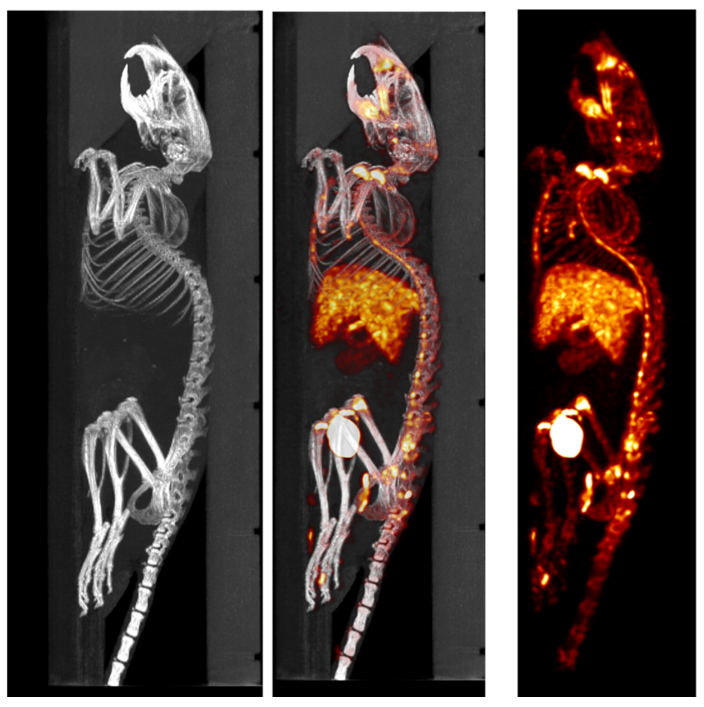

2、和SPECT組合的CT成像

SPECT/CT組合圖像,小鼠的骨骼成像:99mTc-HDP,94.35MBq (2.55mCi) @ start acquisition,采集時間60min。

和SPECT融合.png